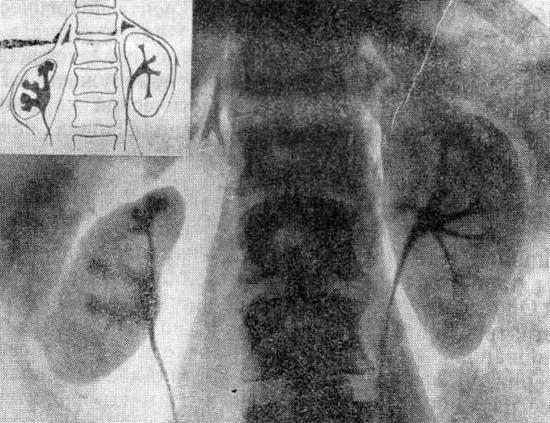

В распознавании врожденных аномалий развития почек решающее значение имеет рентгенорадиологическое исследование. В связи с нарушением функции аномалийной почки у большинства больных с гипертензией наиболее убедительные рентгенологические признаки врожденного дефекта и характер вторичных осложнений удается выявить при инфузионной урографии. Инфузионная урограмма больного К., 47 лет Инфузионная урограмма больного К., 47 лет, с поликистозом почек. Почки значительно …